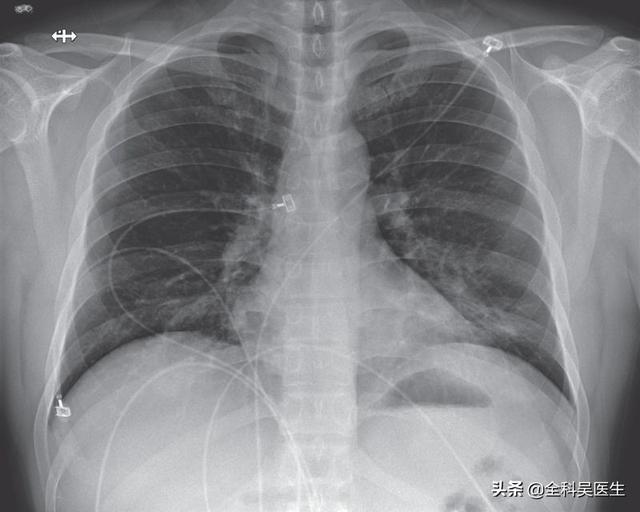

Les radiographies du thorax et l'imagerie par tomodensitométrie des poumons peuvent révéler des zones d'ombre inégales dans les poumons, qui sont évidentes dans les bandes extérieures des poumons, et dans les cas les plus graves, des zones d'ombre solides dans les poumons peuvent être observées.

2. avec des caractéristiques d'imagerie de pneumonie :Cela signifie qu'il y a des changements inflammatoires dans les poumons, présentant de multiples petites ombres en taches et des changements interstitiels, qui sont évidents dans les bandes externes des poumons, et même des changements tels que de multiples ombres en verre dépoli et des ombres d'infiltration dans les deux poumons. Vous vous demandez peut-être pourquoi il y a des changements d'imagerie dans les poumons après une infection. C'est principalement parce qu'une fois que le virus a envahi les poumons, il peut provoquer une congestion et un œdème dans les poumons, qui se traduisent par des ombres de haute densité sur la radiographie ou la tomodensitométrie.

②. Le thorax présente les caractéristiques d'imagerie d'une pneumonie.

Au stade initial, elle présente de multiples petites taches et des changements interstitiels, qui peuvent évoluer vers de multiples taches en verre dépoli et infiltrées dans les deux poumons et, dans les cas les plus graves, des changements solides dans les poumons peuvent se produire, ce qui donne ce que l'on appelle communément les "poumons blancs".